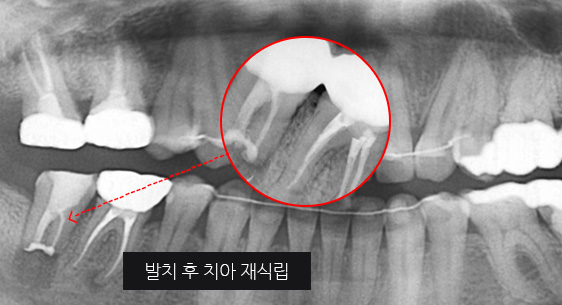

심한 염증으로 치조골이 광범위하게 소실, 아래쪽 신경관이 가까이 있어 치근단수술이 불가능한 상태, 타 병원에서 임플란트 진단을 받았지만,

고운미소치과에서 치아를 발치하고 뿌리 쪽 염증을 제거한 후 발치한 치아를 다시 심는 치아재식술을 시행하였습니다.

기존 신경치료 부위에 염증과 치조골이 소실되고 있는 상태

치아를 발치하고 염증을 제거, MTA로 충전하고 치아를 다시 심음. (난이도 중)